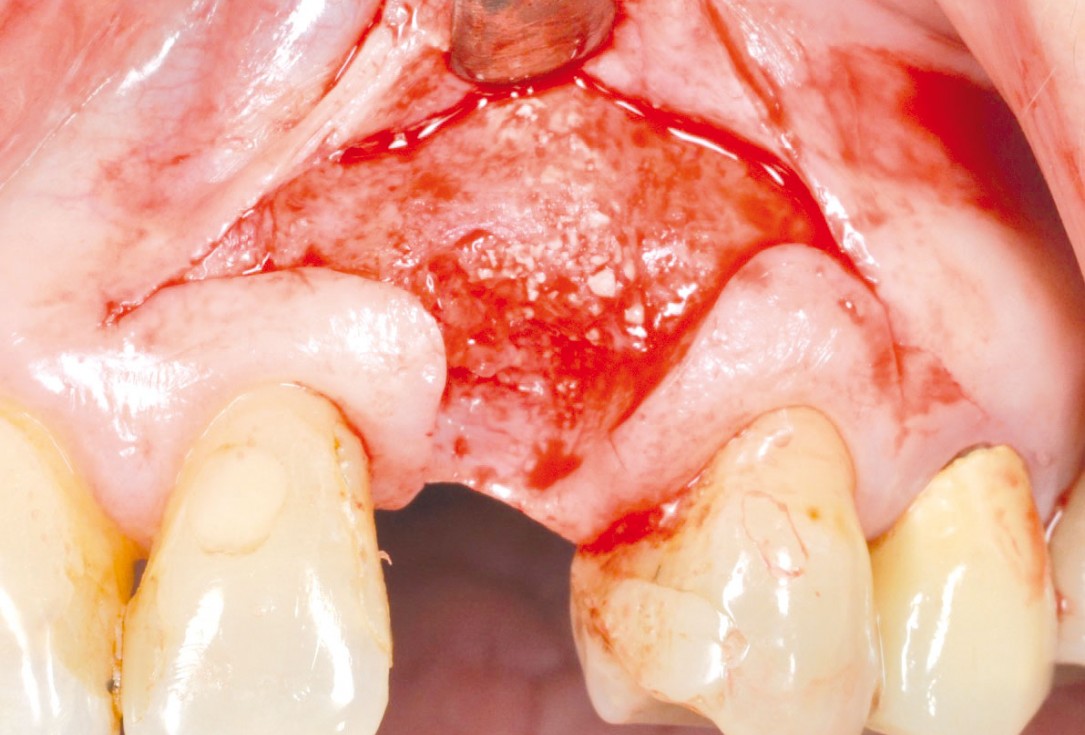

botiss cerabone® & Jason® membrane for horizontal augmentation - Clinical case by Dr. M. Steigmann

Three implants placed in a narrow posterior mandible